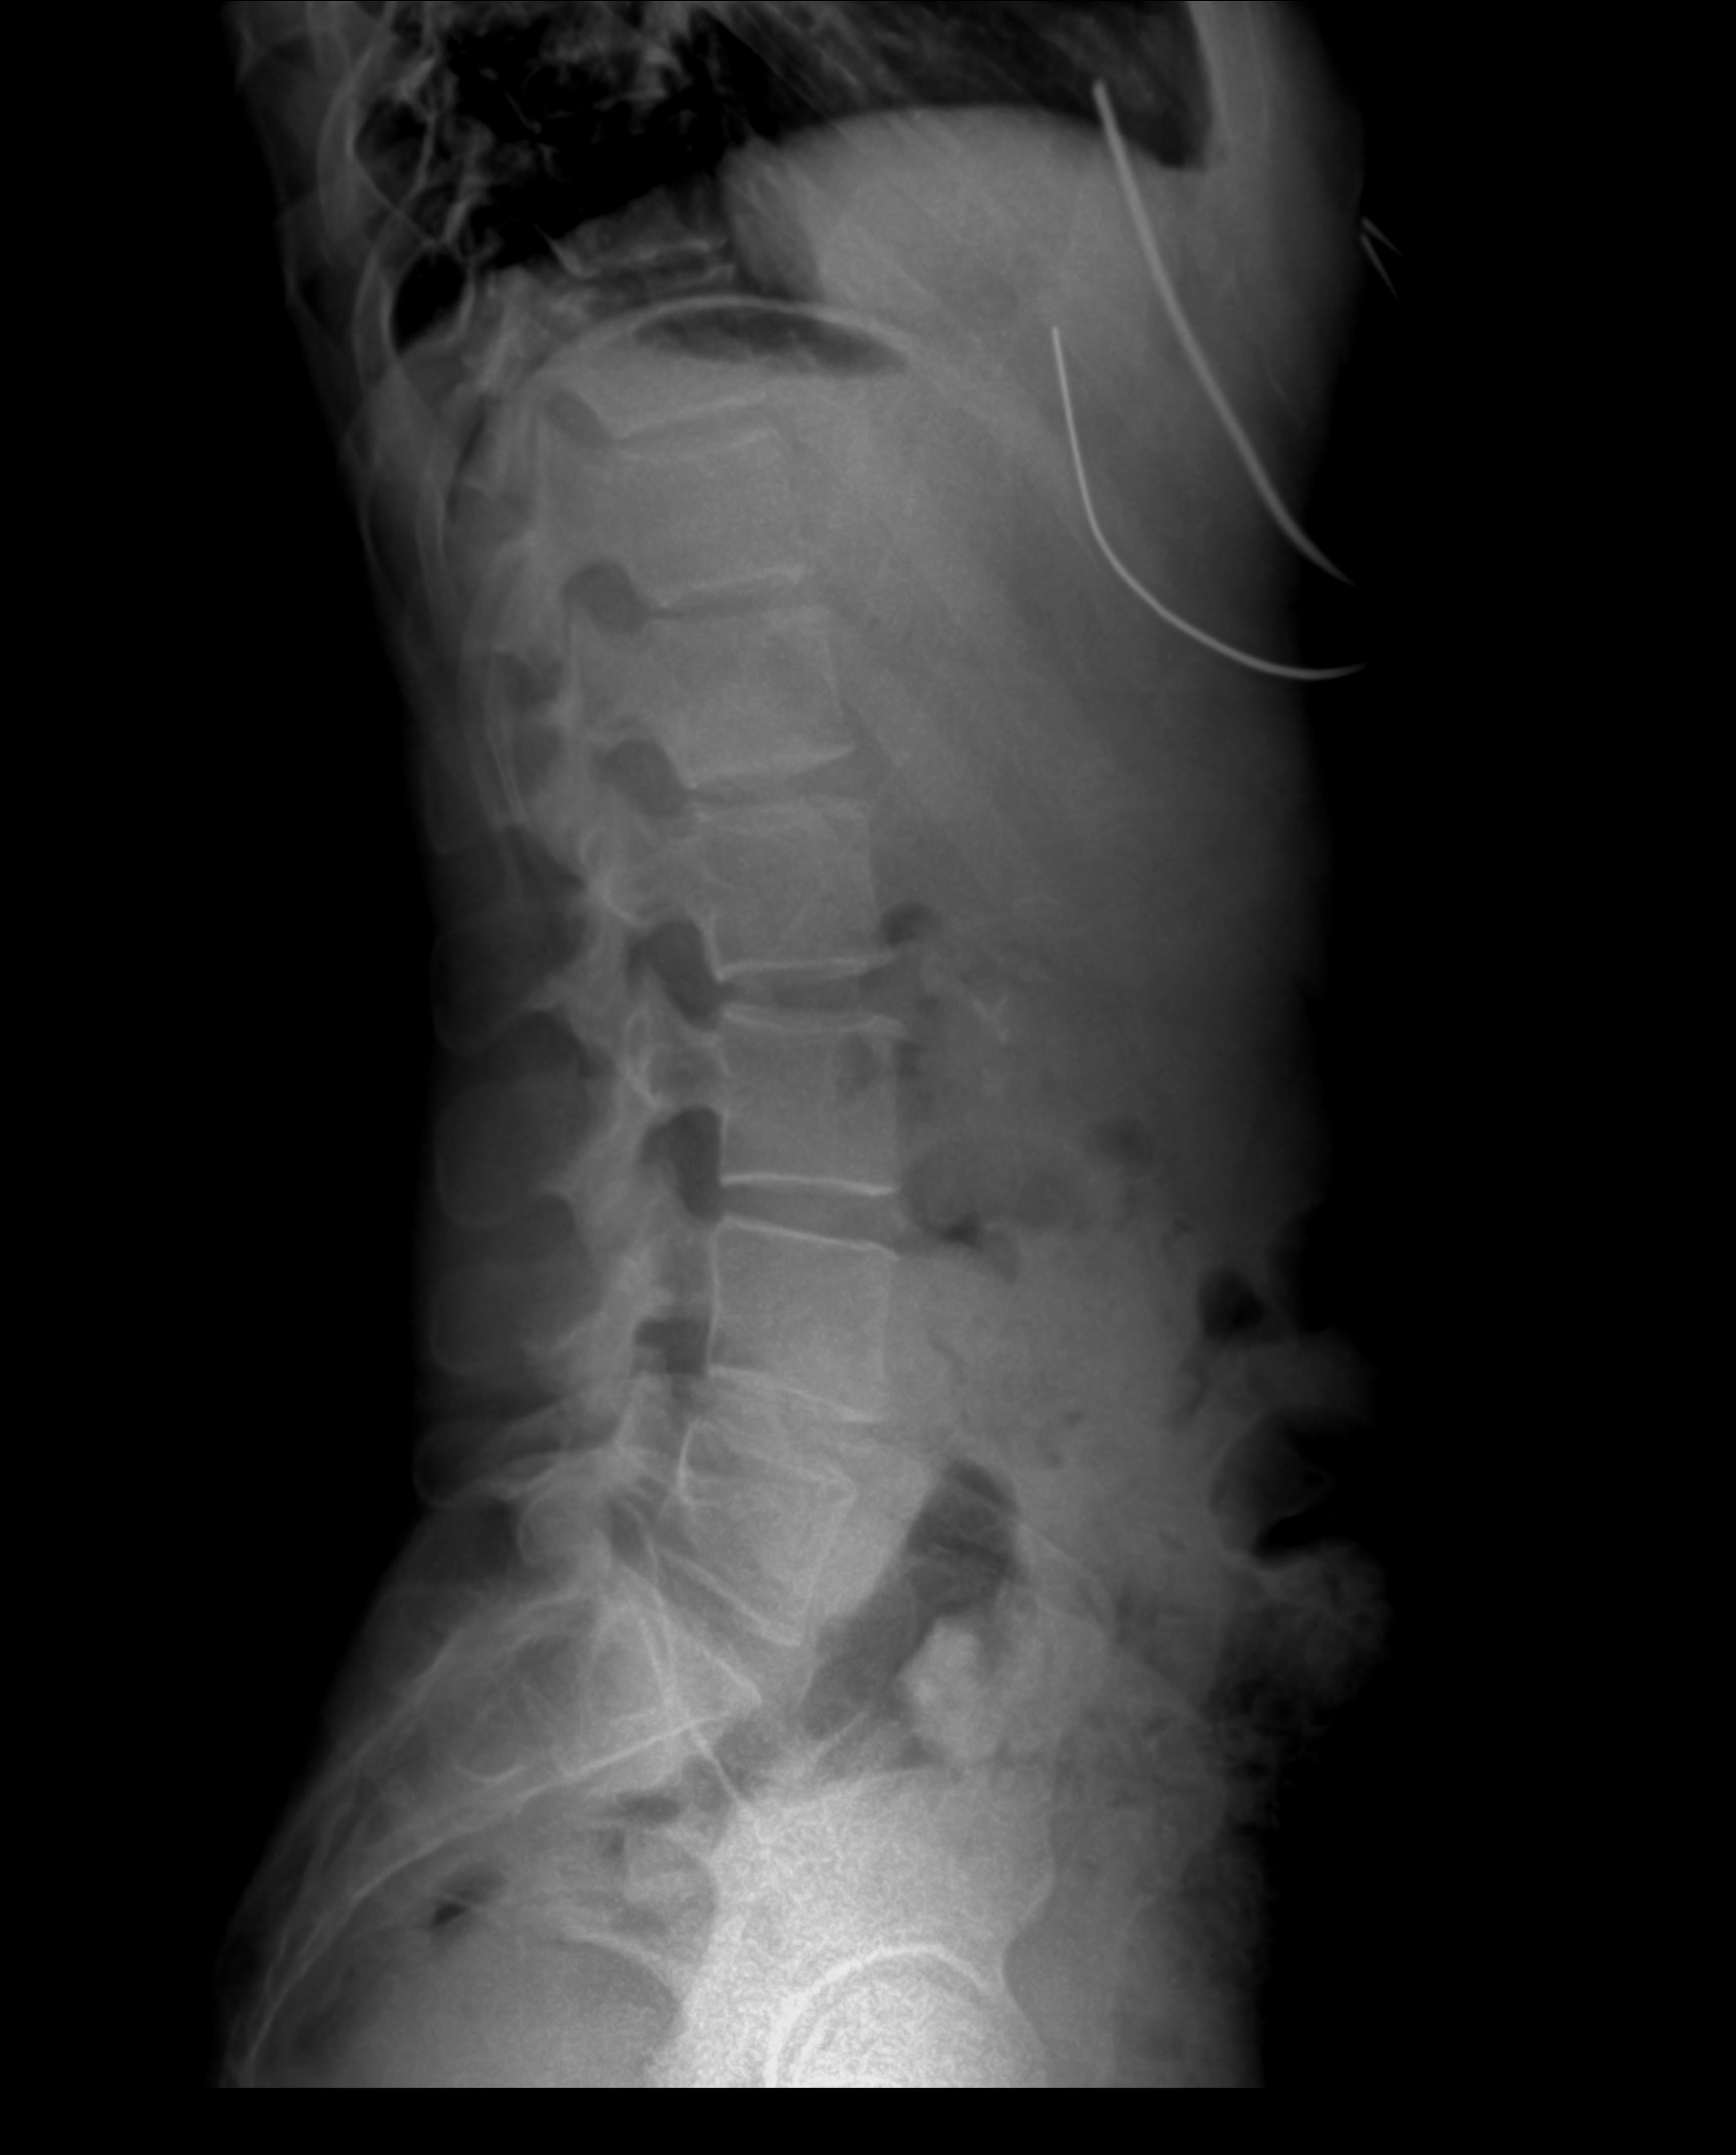

At Ortman Chiropractic in Canistota, South Dakota, we prioritize accurate diagnosis to deliver effective, personalized care. Our X-ray services play a crucial role in this process, allowing us to visualize the spine and extremities with precision. Utilizing state-of-the-art digital X-ray technology, we provide safe, low-radiation imaging that helps identify misalignments, fractures, degenerative changes, and other structural issues. This diagnostic tool is essential for chiropractic evaluations, enabling us to create targeted treatment plans that address the root causes of pain and dysfunction. Whether you're experiencing back pain from daily activities, an injury from farm work, or discomfort in your limbs, our X-rays ensure we have a clear picture of your condition, leading to better outcomes and faster recovery.

X-rays, or radiographs, are a non-invasive imaging method that uses controlled amounts of radiation to produce detailed images of bones and joints. In chiropractic care, they are invaluable for assessing postural abnormalities, spinal curvatures, and joint health without the need for more invasive procedures. At our clinic, X-rays are performed on-site for convenience, with results available quickly to inform immediate care decisions. We adhere to the highest safety standards, using digital systems that minimize exposure—often less than the radiation from a cross-country flight. Our experienced team explains the process beforehand, ensuring you're comfortable and informed every step of the way.